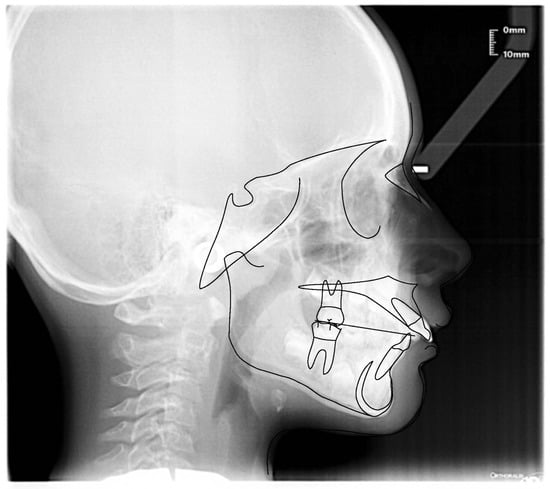

3.1. Clinical Case #1

3.2. Clinical Case #2

3.3. Clinical Case #3

3.4. Clinical Case #4